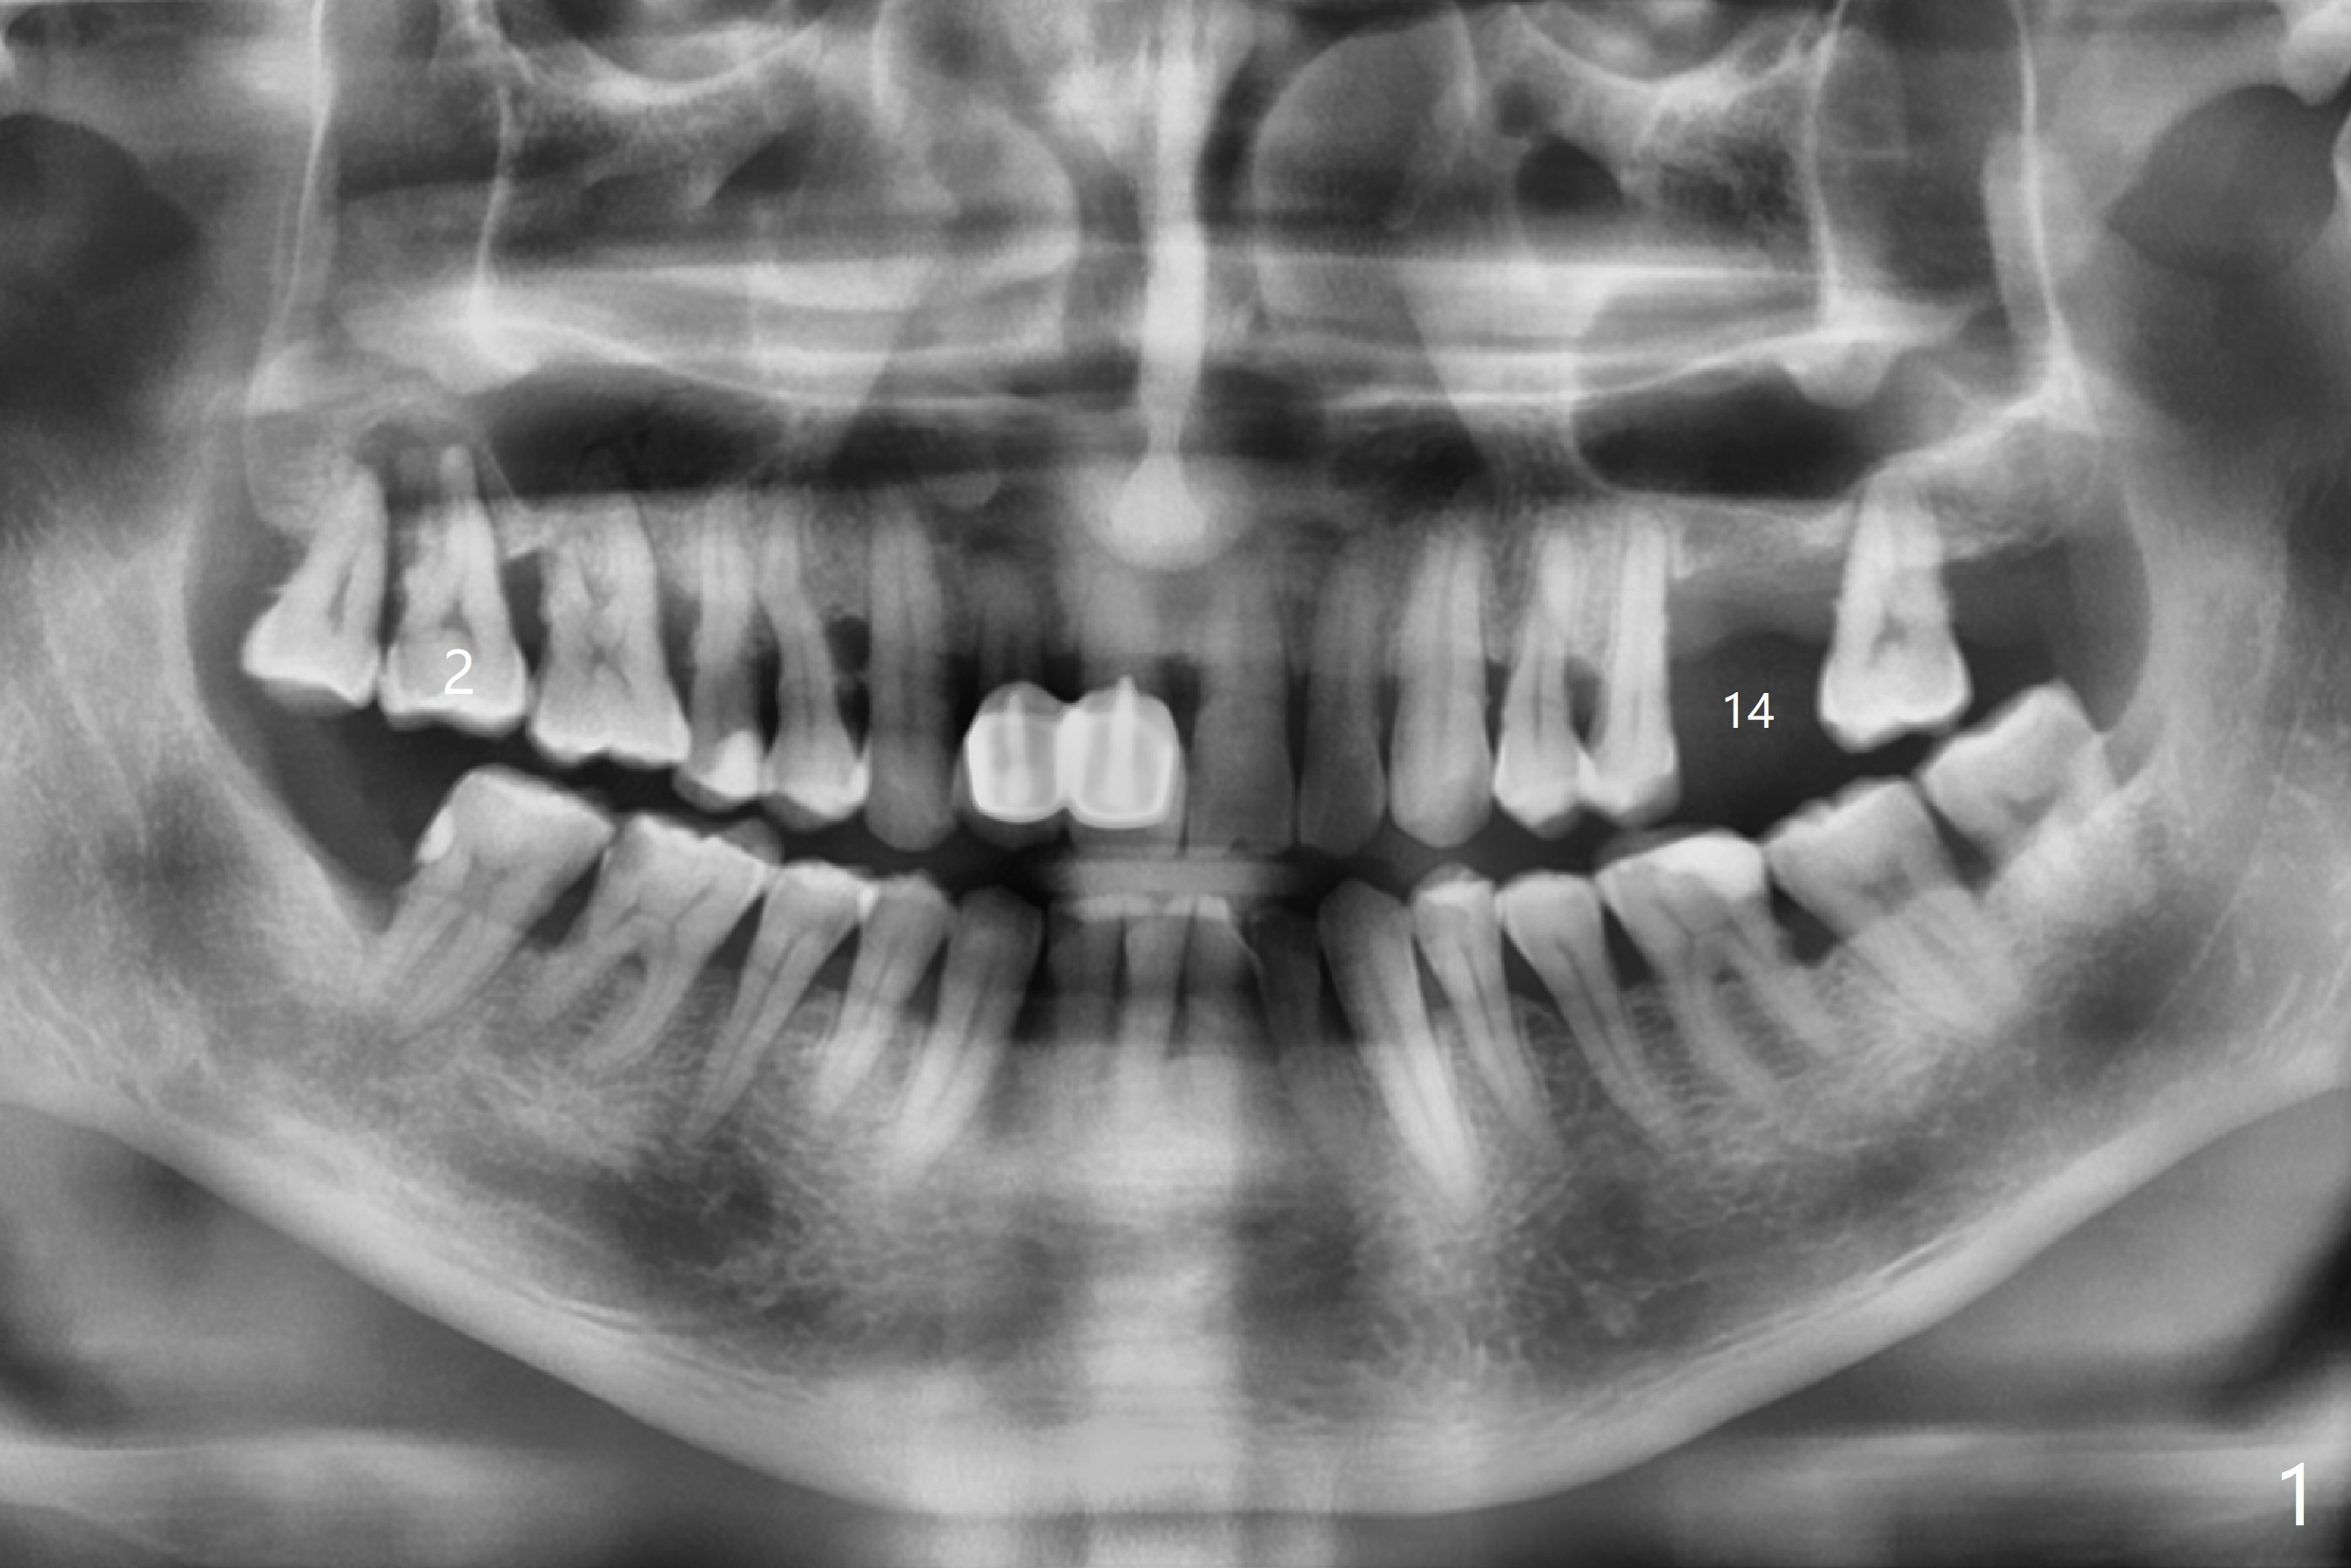

A 54-year-old man presents to office with a request to get a tooth back in the upper left posterior region (Fig.1 #14, wearing RPD). Upon examination, he feels that the tooth #2 is mobile, requiring more urgent care (Fig.2). The infection also involves the tooth #1. Extraction of the latter seems to be imminent. At either site, bone height is limited. Sinus lift is expected with PRF. Place an implant that just passes the sinus floor for stability, e.g., 5-6x10 mm at #2 (Fig.3), but not too long into the sinus. At the 2nd stage (Fig.4), use Magic drill with 2 mm stopper as a tissue punch. Then with 3 mm stopper start osteotomy, followed by Magic lifter, PRF/bone graft and dummy implant or tap. More bone graft and definitive implant. In fact the patient wants to have #14 implant first.